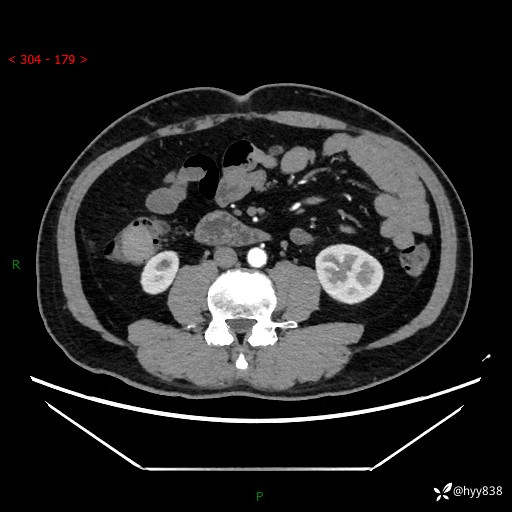

腹部CT增强扫描(外院CT平扫)

两期CT值:75hu 82hu